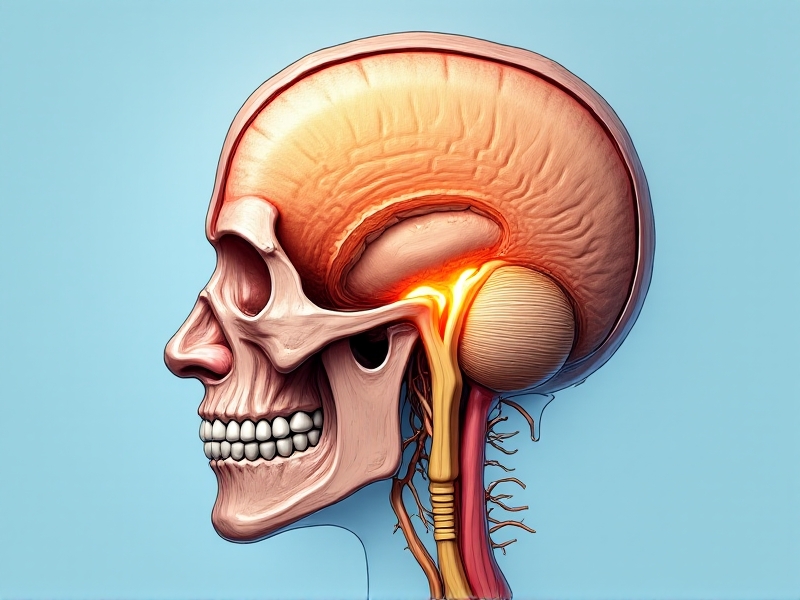

Traditional treatments for migraines include over-the-counter pain relievers, prescription medications, and lifestyle changes. However, these methods are not always effective and can come with side effects. This has led to the exploration of alternative therapies, one of which is transnasal cryotherapy. This innovative approach involves the application of cold therapy to the nasal passages, targeting the trigeminal nerve, which is believed to play a key role in migraine pathophysiology.

Transnasal cryotherapy is a non-invasive treatment that involves the application of cold temperatures to the nasal passages. The concept is based on the idea that cooling the trigeminal nerve, which is responsible for transmitting pain signals from the face to the brain, can help alleviate migraine symptoms. The therapy is typically administered using a specialized device that delivers a controlled stream of cold air or a cryogenic substance directly to the nasal cavity.

The efficacy of transnasal cryotherapy in treating migraines is supported by a growing body of scientific research. Studies have shown that the trigeminal nerve, which is the largest cranial nerve, plays a central role in the development of migraines. When activated, it releases neuropeptides that cause inflammation and dilation of blood vessels in the brain, leading to the characteristic pain of a migraine.

By applying cold therapy to the nasal passages, transnasal cryotherapy targets the trigeminal nerve directly. The cold temperature is thought to inhibit the release of these neuropeptides, thereby reducing inflammation and constricting blood vessels. This not only alleviates pain but also helps to prevent the onset of migraines in some cases. Furthermore, the therapy has been shown to have a calming effect on the nervous system, which can be beneficial for individuals who experience migraines triggered by stress or anxiety.